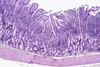

Cross section of the esophageal mucosa. The three layers of the mucosa are indicated. The submucosa appears at the lower third of the image . In this part of the esophageal wall, esophageal gland proper (G) is visible.